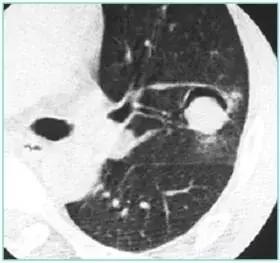

CT征象一:树芽征

由终末细支气管和肺泡腔内病变形成的小结节影与分支细线影构成的酷似春天的树枝发芽状,称“树芽征”(tree-in-bud)

CT表现:多在肺外围支气管末梢呈2-4mm大小结节与树枝状的高密度影。

意义:多表明有小气道病变如:细支气管炎症、弥漫泛发性细支气管炎及肺结核病灶或播散等

末梢细支气管扩张形成粘液栓——酷似“树芽征”

末梢细支气管与肺泡结核灶及播散——酷似“树芽征”

“树芽征”:活动性肺结核支气管播散;泛细支气管炎